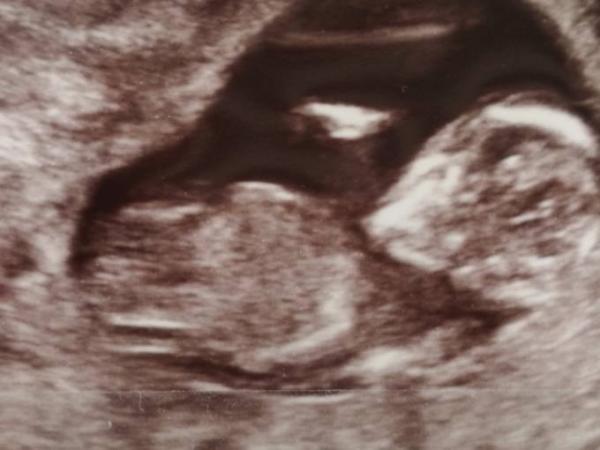

Halli Hallo Ich wollte mal wissen was ihr denkt was das Baby für ein Geschlecht haben könnte. Freue mich auf Antworten LG

Bild zu Geschlecht erkennbar??? - Schwanger - wer noch? Rund um die Schwangerschaft

Naja, schwer zu sagen. Es dreht uns ja den Rücken zu :)

Das ist aus der Perspektive nicht zu erkennen...

Mit einer 50-50 Chance wird es ein Mädchen